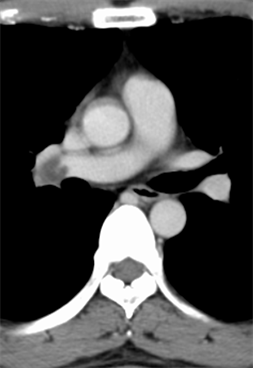

A 47-year-old man was referred to our institute with an enlarging left RCC. Computed tomography scanning revealed a large enhanced mass in the left kidney (Figure 1(a)) and local extension into the infrahepatic IVC (Figure 2) with pulmonary tumor embolism (Figure 3(a)). The embolism was located at the proximal portion of the right pulmonary artery, with no suspicious lesions in the left lung. As the mass of the RCC had been rapidly increasing in size for the past 2 months, early surgery was scheduled.

After sufficient anticoagulant treatment, the patient was discharged without any complications (Figure 1(b), Figure 3(b)). He is currently doing well with no evidence of recurrent disease or other metastases at a follow-up of 10 months. Follow up computed tomography revealed no recurrences and other metastases.

Figure 3. (a) Preoperative computed tomography scan showing tumor embolism in the right pulmonary artery (white arrow head); (b) Postoperative computed tomography scan showing no pulmonary tumor emboli.